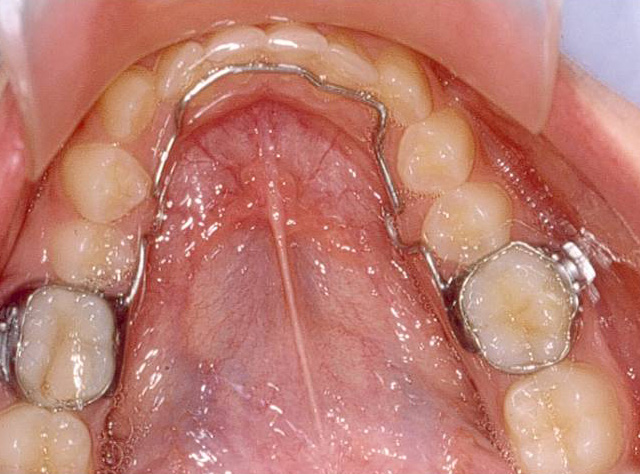

In the same way as Luis, we place first space maintainers and we take advantage of the size difference between the milk molars and the permanent premolars which replace them.

We recommend the use of fixed retainers of wire “on the inner surface” to prevent these teeth to move again.